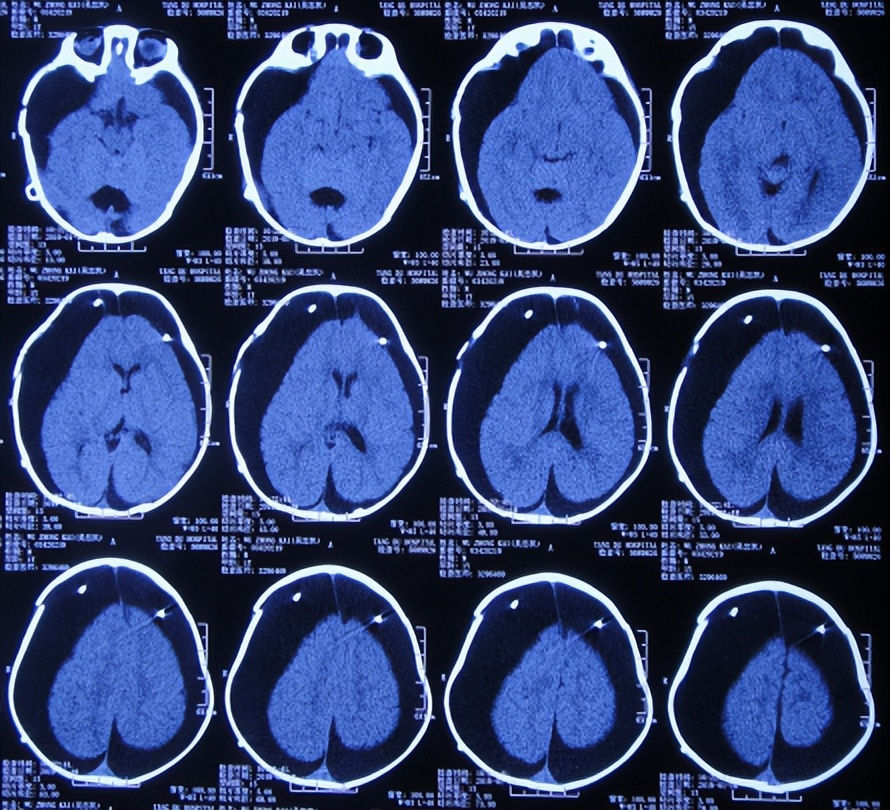

入院后5天即2018年9月18日,进行了双侧颞叶蛛网膜囊肿脑池沟通术。但术后次日,患儿出现恶心呕吐,复查头颅CT示双侧硬膜下积液( 图-3 )。

图-3: 2018年9月19日头颅CT

2018年9月27日(蛛网膜囊肿脑池沟通术后9天),查头颅CT示硬膜下积液反增多( 图-4 )。

图-4: 2018年9月27日头颅CT

2018年10月20日(蛛网膜囊肿脑池沟通术后32天),查头颅影像示硬膜下积液持续进一步增多( 图-5、图-6 )。

图-5: 2018年10月20日头颅CT

图-6: 2018年10月20日头颅影像